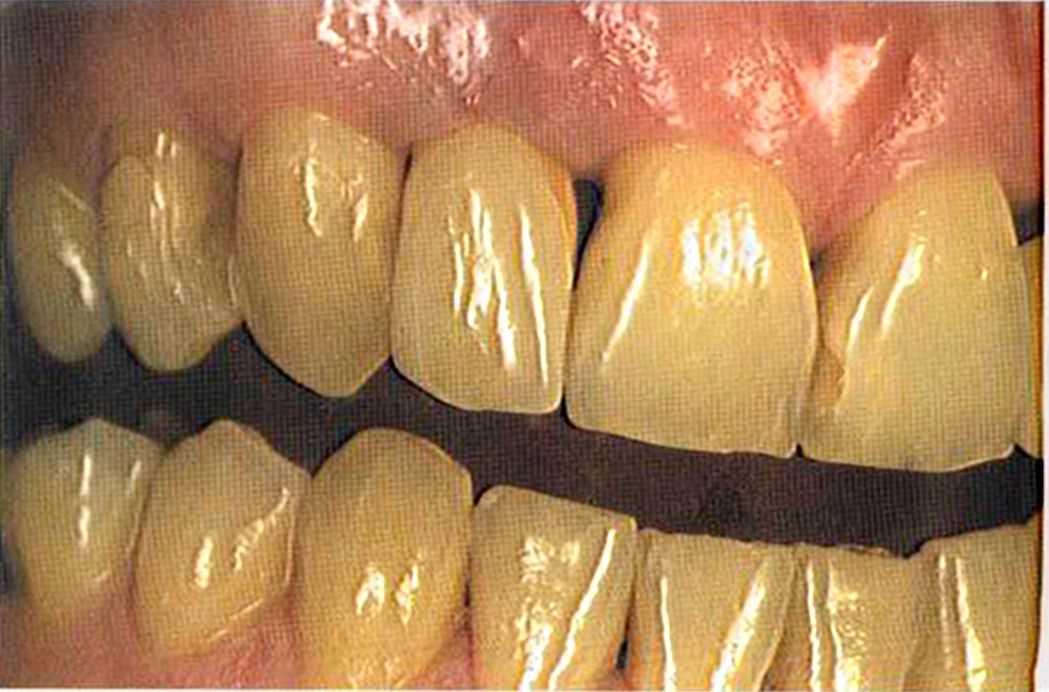

Результат с использованием In-Ceram развеял все сомнения, и решение об изготовлении коронки на другой боковой резец не заставило себя долго ждать.

После того как мы определит цвет зуба, решено быо сначсьа изготовить одну коронку.

Го то вый результат. Зуб 21 со штифтом из Zirconia. От 12 до 21 изготовлены три отдел1>ные коронки 1п-Сегат. Все зафиксировано в полости рта на цемент Panavia ТС.